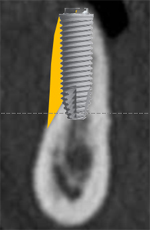

- インプラントを埋入することはできるが、一部の骨量が不足している場合、埋入と同時に骨造成を行う方法。手術が一度で済む。

ボーングラフトは、十分な量の骨が得られない場合に、骨をブロックで切り出し、移植することで必要な骨を作り出します。

- 上顎前歯部を抜歯すると大きな骨吸収を予測したため、下顎臼後三角部より骨片を採取し、抜歯時にインプラント埋入と同時に骨造成を行なった